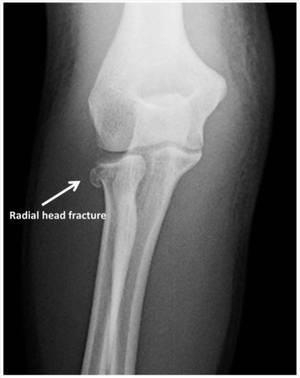

Radial head fracture (peds)

- AP and lateral elbow xray